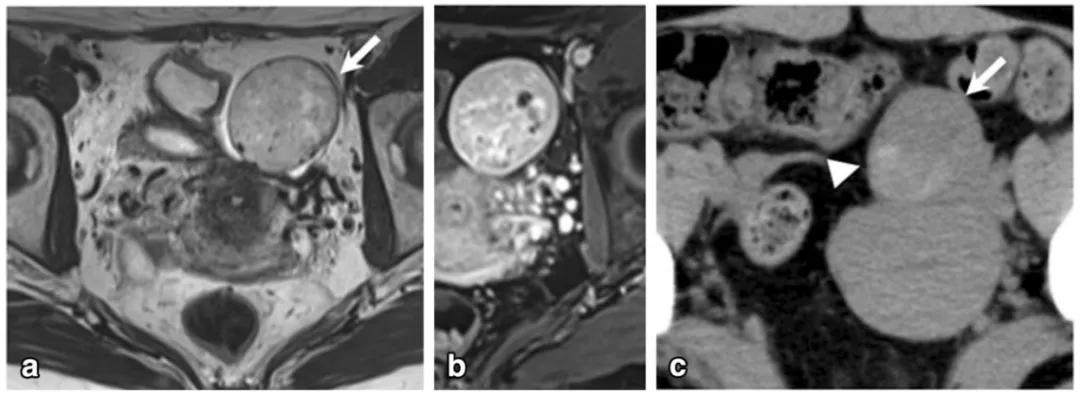

女,68 岁,左卵巢 Brenner 瘤。T2WI 显示左侧卵巢巨大低信号肿物(图 a),CT 扫描显示 8 年后肿物增大、多发钙化、发生囊变(图 b)。

女性,36 岁,睾酮升高,类固醇细胞瘤。T2WI 示右卵巢可见不均匀稍高信号肿物(图 a),增强扫描早期明显强化(图 b)。T1WI 同相位(图 c)及反相位(图 d)可显示肿物内脂质成分,相应 CT 图像呈低密度(图 e)

女,50 岁,卵巢甲状腺肿。左卵巢肿物,T2WI 呈不均匀稍高信号(图 a),增强扫描早期明显强化(图 b),CT 扫描显示囊内成份密度稍高(图 c)。